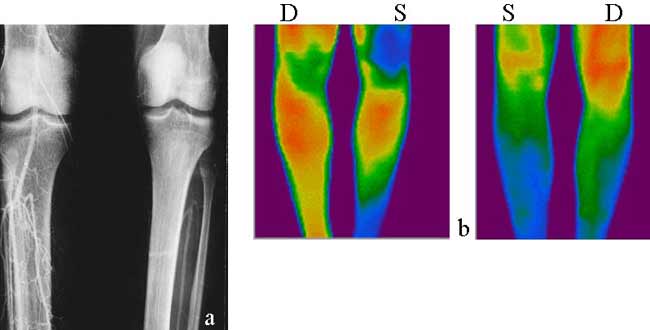

Рис. 4. Облитерирующий тромбангит. (а) Артериография. Непроходимость левой бедренной и подколенной артерии. Задняя берцовая артерия облитерирована тотально на левой и в нижней трети на правой голени. Передняя берцовая артерия проходима на левой и облитерирована в дистальной трети правой голени. (б) Термография. Нормальная вентральная термограмма правой и умеренная гипотермия нижней трети левой голени. Гипотермия дорзальных поверхностей обеих голеней, более выраженная слева. ТБИ на правой ПБА 0.60, на левой 0.51. ТБИ на правой ЗБА 0.48, на левой 0.32.